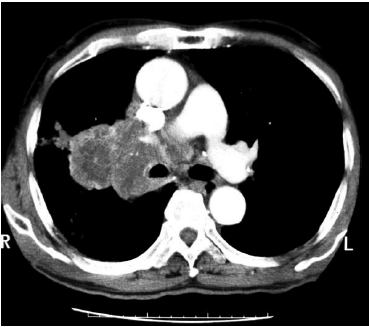

Considere a imagem que segue:

Fonte: http://rle.dainf.ct.utfpr.edu.br/hipermidia/images/documentos/Patologias_toracicas_achados_de_imagem.pdf

A figura acima representa um exame por tomografia computadorizada (janela para mediastino) demonstrando um carcinoma broncogênico. O exame indicou a lesão como inoperável devido à invasão da: